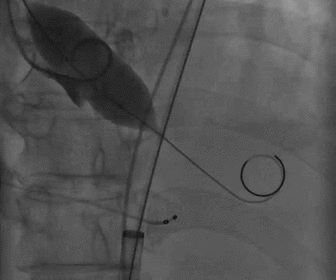

根部造影

球囊预扩

胶囊腔定位

瓣膜释放

造影观察瓣膜形态

术后造影及超声探查未见瓣周漏,跨瓣压差术前72mmHg,术后几乎无压差,术中及术后未出现相关并发症,手术圆满完成。